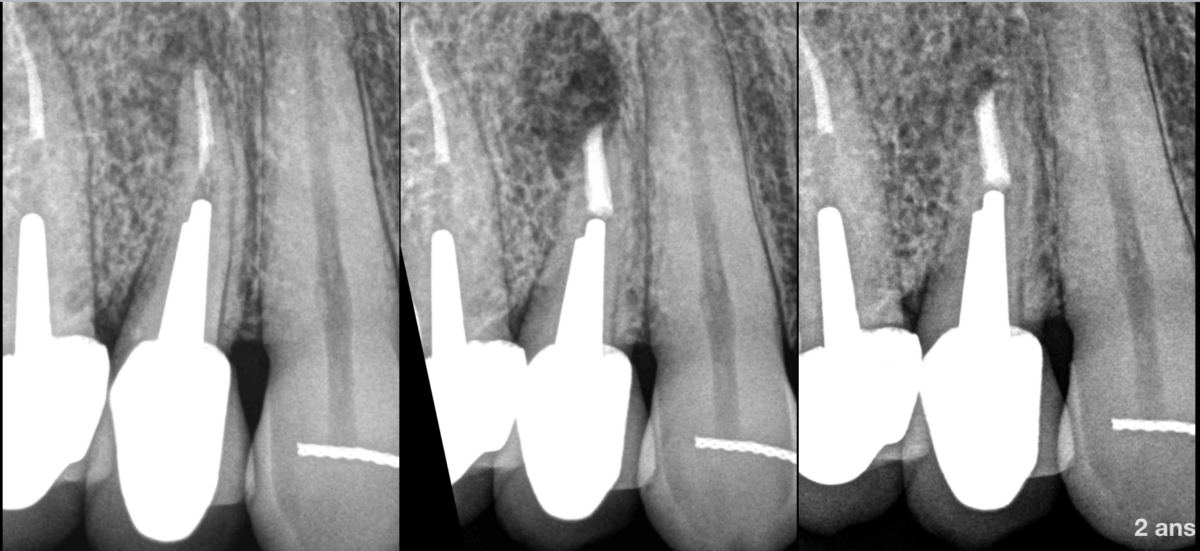

🔍 𝐎𝐮̀ 𝐬𝐞 𝐩𝐥𝐚𝐜𝐞 𝐥𝐚 𝐦𝐢𝐜𝐫𝐨𝐜𝐡𝐢𝐫𝐮𝐫𝐠𝐢𝐞 𝐝𝐚𝐧𝐬 𝐥𝐞 𝐠𝐫𝐚𝐝𝐢𝐞𝐧𝐭 𝐭𝐡𝐞́𝐫𝐚𝐩𝐞𝐮𝐭𝐢𝐪𝐮𝐞 𝐞𝐧𝐝𝐨𝐝𝐨𝐧𝐭𝐢𝐪𝐮𝐞, 𝐩𝐚𝐫 𝐫𝐚𝐩𝐩𝐨𝐫𝐭 𝐚𝐮 𝐫𝐞𝐭𝐫𝐚𝐢𝐭𝐞𝐦𝐞𝐧𝐭 𝐜𝐚𝐧𝐚𝐥𝐚𝐢𝐫𝐞 𝐝𝐚𝐧𝐬 𝐜𝐞 𝐜𝐚𝐬 ?

❓ Avant ou après le retraitement canalaire ?

❓ Autrement dit, qui consomme le plus de capital dentinaire entre les deux ?